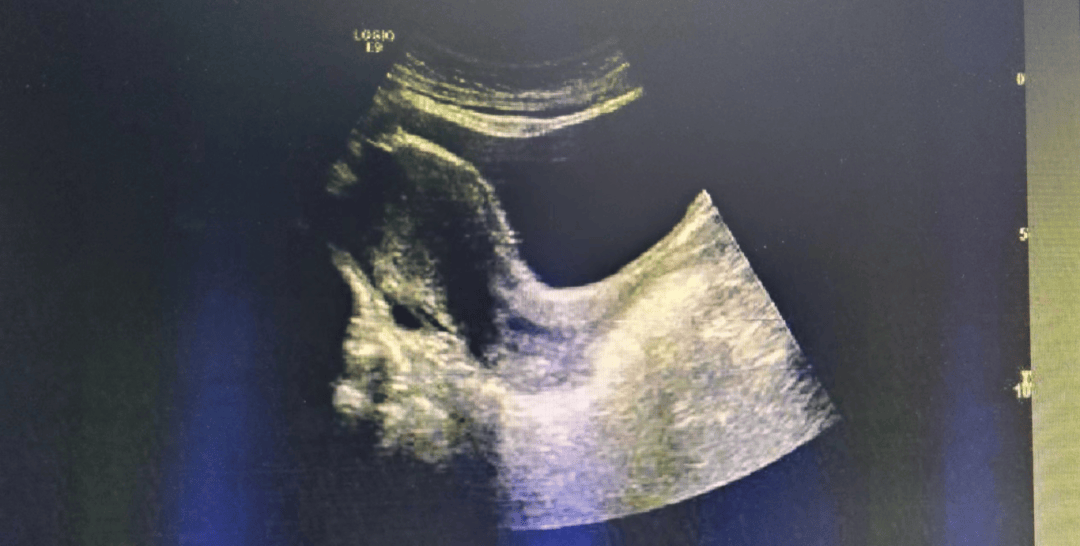

像打开了窗户一样,让超声波畅通无阻的穿过,直接到达子宫和卵巢,所以